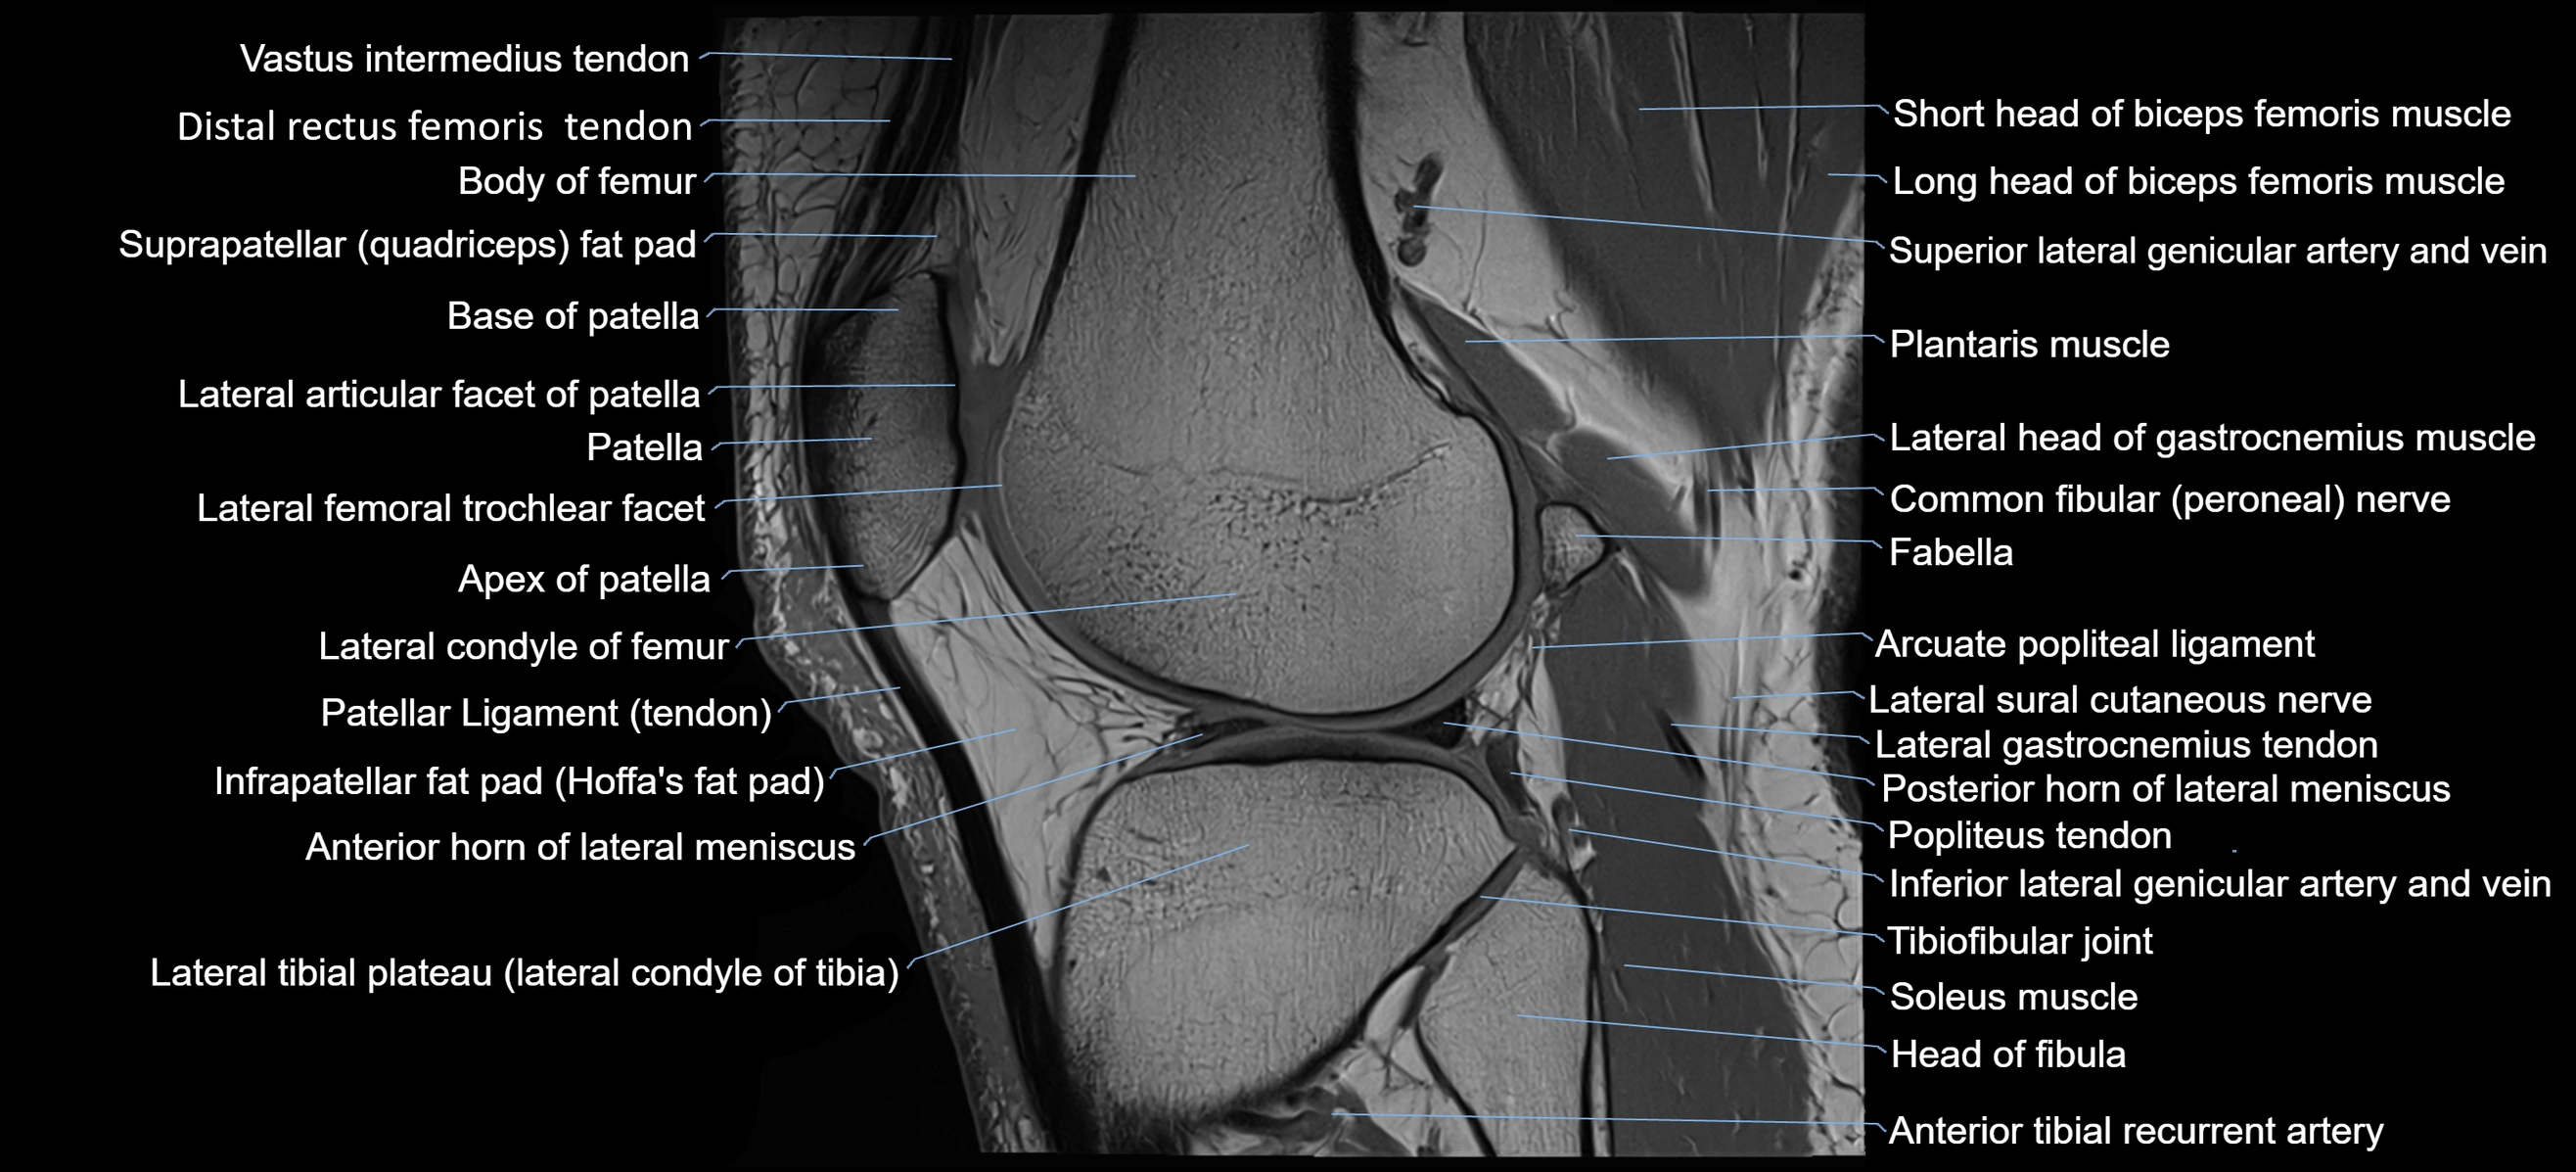

- Anterior horn of lateral meniscus

- Apex of patella

- Base of patella

- Distal rectus femoris tendon

- Distal vastus intermedius tendon

- Head of fibula

- Infrapatellar fat pad

- Lateral articular facet of patella

- Lateral condyle of femur

- Lateral gastrocnemius tendon

- Lateral head of gastrocnemius muscle

- Lateral sural cutaneous nerve

- Patellar tendon (patellar ligament)

- Plantaris muscle

- Popliteus tendon

- Posterior horn of lateral meniscus

- Soleus muscle

- Suprapatellar fat pad

- Tibial tuberosity

- Transverse ligament of knee